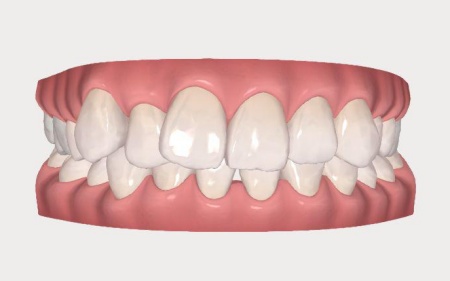

インビザラインGoでは、治療を始める前に歯の動きをシミュレーションで確認することができます。

まず口腔内スキャナー「iTeroエレメント」という光学印象機器を使用して、お口の中を撮影し歯並びのデータを取得しました。

iTeroエレメントは従来の粘土のような材料で型取りをする方法とは異なり、カメラで歯並びを読み取り立体的なデータとして記録する装置です。

取得したデータは専用ソフトウェア「クリンチェック」で解析し、歯がどのように動いていくかを3Dのシミュレーションとして作成しました。

作成したシミュレーションを患者様と一緒に確認したところ、患者様は「上の歯並びだけを整えたい」と希望されました。